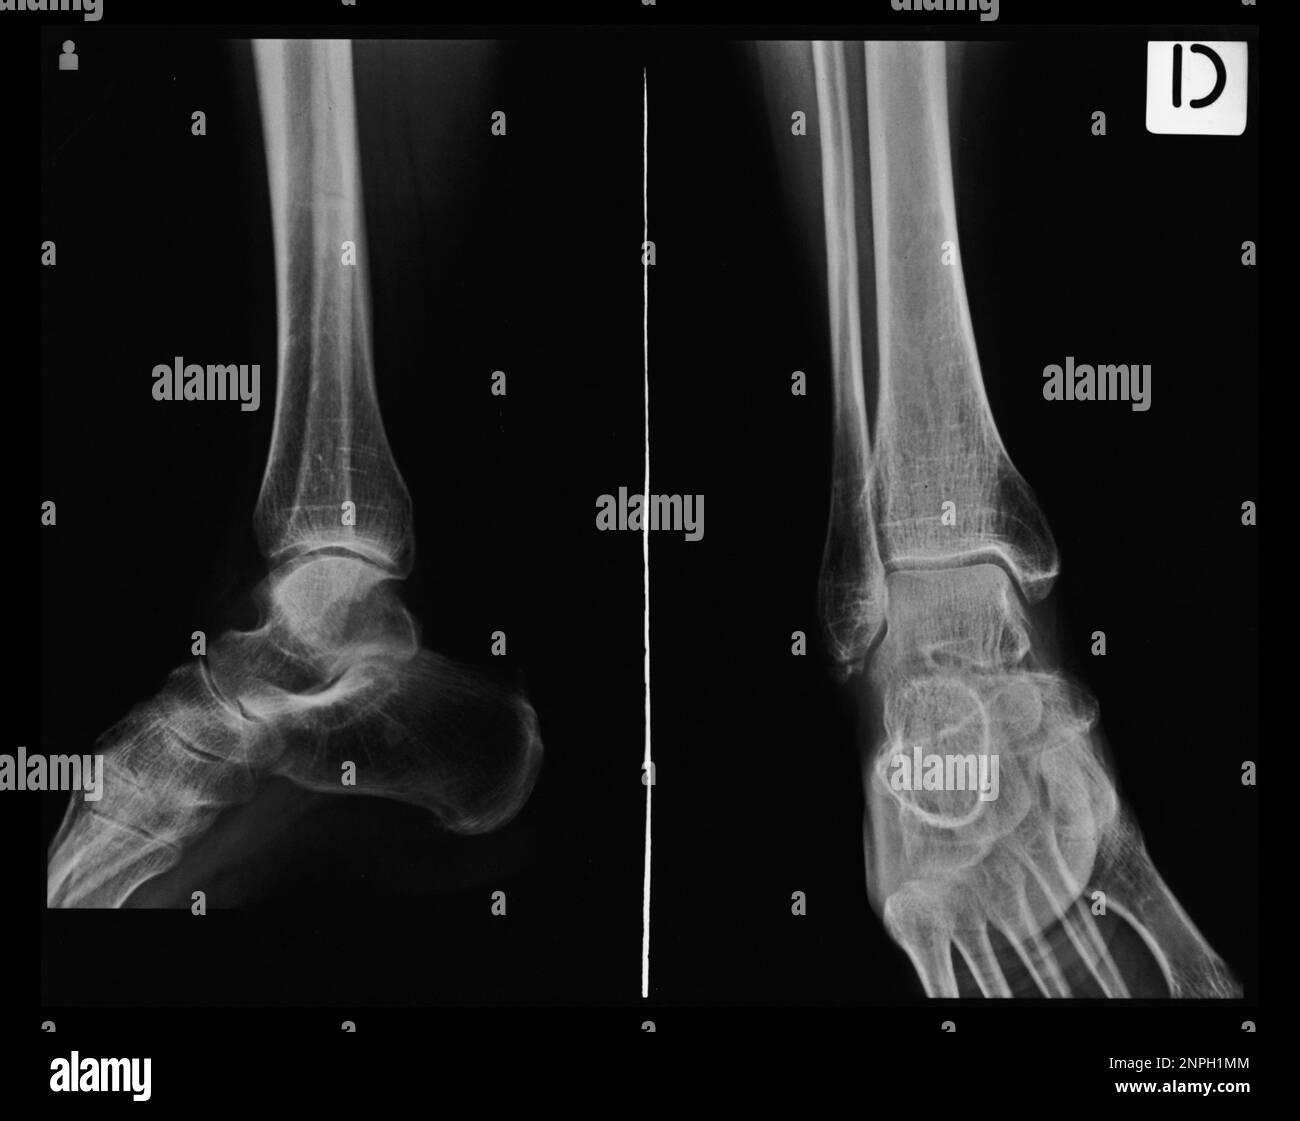

Xray Tarsal and Ankle Front. Stock Image Image of lateral Tarsal Bones Labeled X Ray They are collectively known as the. What are the tarsal bones, and where are they located. The tarsal bones of the foot are organised into three rows: Tali 4), historically known as the astragalus, is a tarsal bone in the hindfoot that articulates with the tibia, fibula,. Outline the cortices of the talus, calcaneus, and navicular bones. The proximal tarsal. Tarsal Bones Labeled X Ray.

From www.theskeletalsystem.net